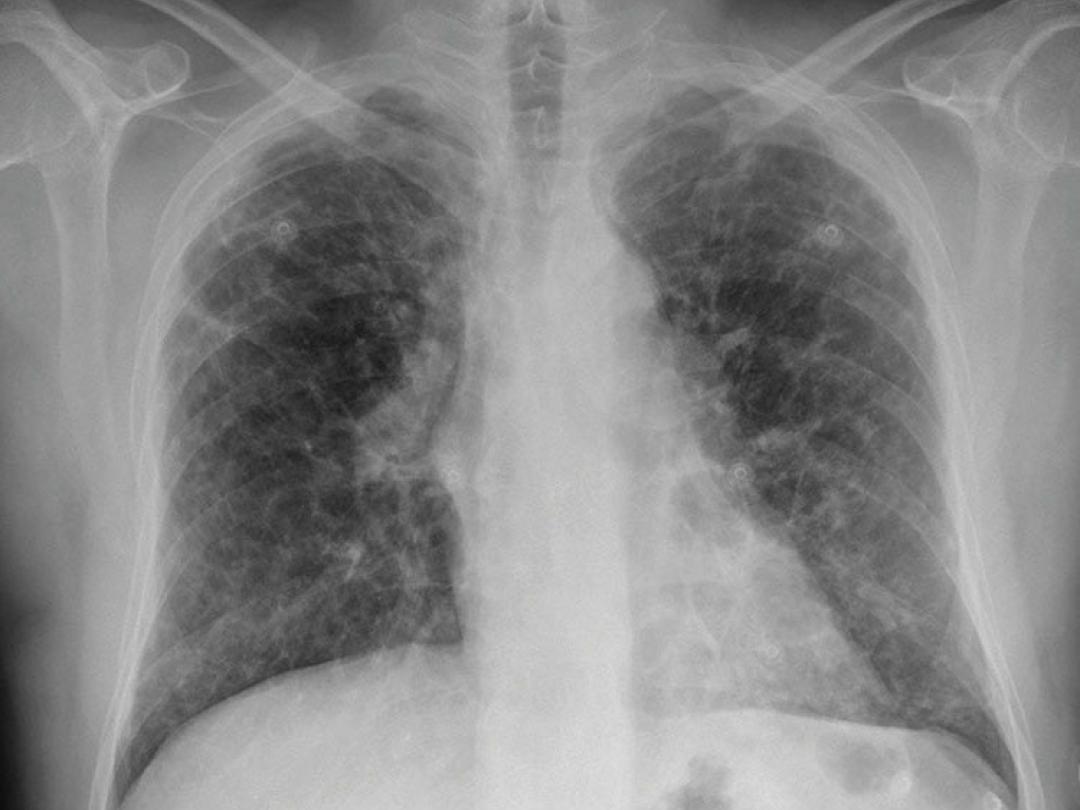

Thoraxfoto

Beroepsmatige blootstelling aan fijne stofdeeltjes is een belangrijke risicofactor voor de ontwikkeling van verworven interstitiële longaandoeningen. Afhankelijk van het type ingeademde stof zijn er verschillende vormen van ‘stoflong’ (pneumoconiose) te onderscheiden. In deze casus beschrijven we een patiënt met pneumoconiose door inhalatie van silicadeeltjes (kwartsstof).

Patiënt, een 57-jarige man, was door de huisarts verwezen naar de longarts omdat hij sinds 4-5 maanden klachten had van progressieve dyspnée d’effort en droge hoest. De patiënt had een voorgeschiedenis van nicotineabusus (20 pakjaren). Uit de beroepsanamnese bleek dat hij tot tien jaar geleden bijna vijf jaar lang als betonstraler had gewerkt. Betonstralen is een reinigingsmethode waarbij een straalmachine kogeltjes afvuurt op beton, waardoor de oppervlaktestructuur verandert maar ook stofdeeltjes vrijkomen. Beschermingsmaatregelen waren niet consequent toegepast.

Bij lichamelijk onderzoek had de patiënt een niet-afwijkende zuurstofsaturatie. Bij longauscultatie hoorden wij beiderzijds fijne inspiratoire crepitaties. Het longfunctieonderzoek bevestigde dat de patiënt COPD had (Gold-stadium II)…